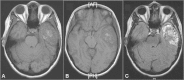

Background Aneurysmal bone cysts (ABCs) are benign bony lesions that rarely affect the skull base. Very few cases of temporal bone ABCs have been reported. We describe the first case of a temporal bone ABC that was thought to be consistent with a meningioma based on preoperative magnetic resonance imaging (MRI) findings. Clinical Presentation An otherwise healthy 23-year-old woman presented with a pulsatile noise in her left ear and a 4-week history of throbbing headache with nausea. There was no associated emesis, visual or auditory changes, or other neurologic features. Neurologic examination revealed a left lower motor neuron facial paresis. Computed tomography and MRI studies demonstrated a large lesion in the left middle cranial fossa skull base with erosion of the petrous temporal bone. Based on the presence of a "dural tail" on preoperative contrast-enhanced T1-weighted imaging, the lesion was interpreted to likely be consistent with a meningioma. An orbitozygomatic approach was utilized for surgical excision. Histopathologic evaluation was consistent with an ABC. Conclusion Postoperatively the patient had improvement in the lower motor neuron facial paresis. It is important to consider ABC in the differential diagnosis of intracranial lesions accompanied by the dural tail sign on MRI.